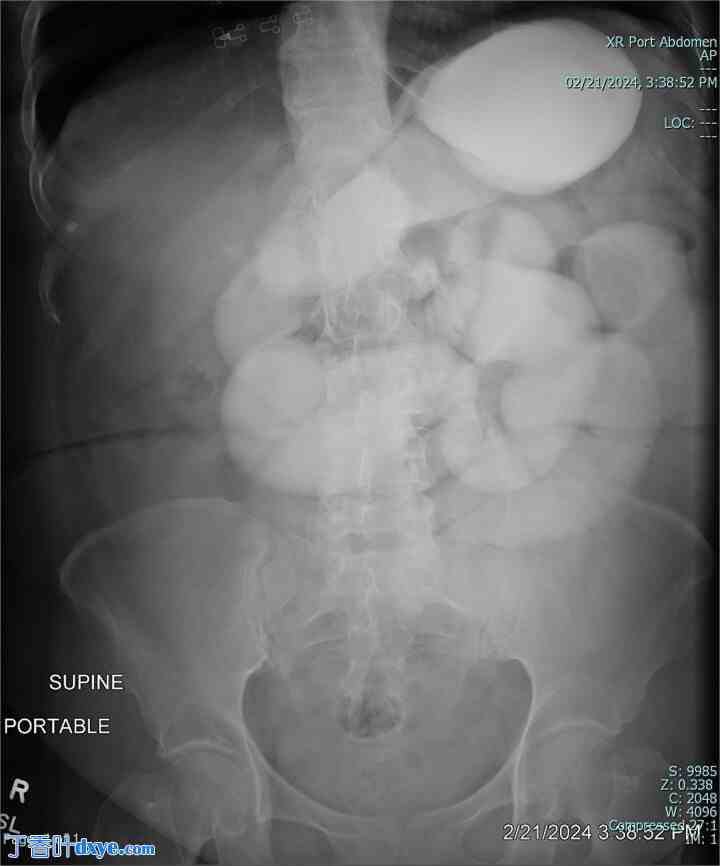

患者因疑似粘连性小肠梗阻而入院接受保守治疗。她接受了静脉补液和鼻胃管减压治疗。住院第 2-4 天,她开始感觉好些,并开始排气。胃泛影葡胺激发试验显示造影剂通过小肠进入结肠(图 3 和 4)。然而,住院第 5 天,她的肠道功能停止,腹痛加剧,心动过速和白细胞增多(WBC 16 K/μl)。

图 3。

胃泛影葡胺激发试验显示造影剂在连续成像中通过小肠进入结肠 [300 × 361 mm (72 × 72 DPI)]。